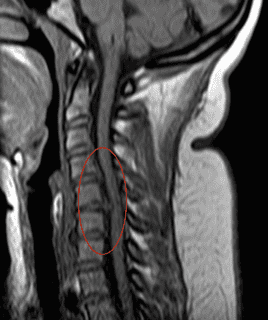

Ante a suspeita de uma afecção raquidiana, a Ressonância Magnética (RM) ou a Tomografia Computadorizada podem mostrar lesões, que se correlacionem com os sintomas. Quando se trata de hérnias de disco cervicais ou de uma estenose do canal vertebral cervical, a decisão quanto ao tratamento a ser realizado se baseia sempre no aspecto clínico e na avaliação feita no(a) paciente. Estes exames indicam o motivo destas alterações e onde seria preciso intervir, mas, em nenhum caso, correspondem a uma indicação cirúrgica.

-Caso Nº 17635